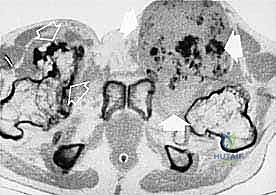

2. ساركوما الأنسجة الرخوة (Soft Tissue Sarcomas)

تنشأ في الأنسجة الداعمة المحيطة بالعظام. تشمل:

* ساركوما الخلايا الزليليّة (Synovial Sarcoma).

* الساركوما الشحمية (Liposarcoma).

* الساركوما العضلية الملساء (Leiomyosarcoma).

تتميز هذه الأورام بقدرتها على اختراق الأنسجة المجاورة وتكوين ما يُعرف بـ "المنطقة التفاعلية" (Reactive Zone) أو الكبسولة الكاذبة، والتي تحتوي غالباً على خلايا سرطانية مجهرية. هذا المفهوم البيولوجي هو ما يوجه الدكتور محمد هطيف في تحديد مدى الاستئصال الجراحي.